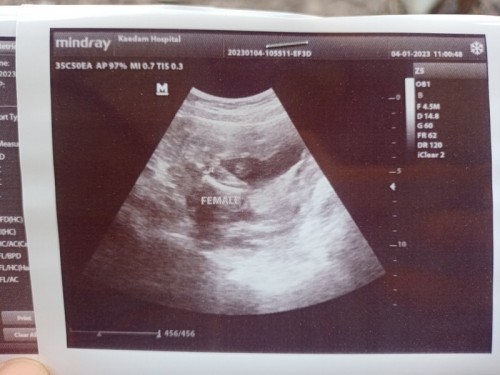

สอบถามแม่ๆบ้านอื่นค่ะ คุณหมอบอกว่ามีโอกาสเป็นผู้หญิง 95% รบกวนแม่ๆช่วยดูหน่อยค่ะ ภาพมันไม่ค่อยชัดเลย

เราว่าญ ค่ะ กลีบชัดมาก